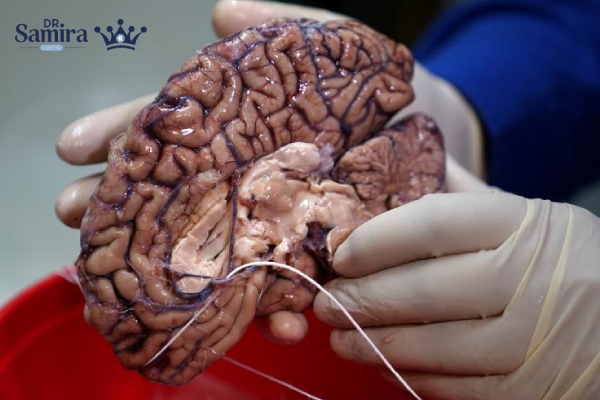

لنفوم مغز یکی از زیرگروههای لنفوم غیرهوچکین است که بهطور مستقیم در مغز، نخاع، پردههای مغزی یا چشم ایجاد میشود. این نوع لنفوم را «لنفوم اولیه سیستم عصبی مرکزی» نیز مینامند. برخلاف بسیاری از سرطانهای دیگر، لنفوم مغز از خارج به مغز گسترش نمییابد، بلکه از ابتدا در بافتهای عصبی مرکزی تشکیل میشود. ویژگی مهم این سرطان، رشد نسبتاً سریع و حساسیت بالای آن به درمانهایی مانند شیمیدرمانی و رادیوتراپی است.

آیا جراحی برای لنفوم مغز استفاده میشود؟

برخلاف بسیاری از تومورهای مغزی دیگر، جراحی نقش محدودی در درمان لنفوم مغز دارد. علت اصلی این است که این تومورها به صورت منتشر رشد میکنند و مرز مشخصی برای برداشت جراحی ندارند. با این حال، در برخی موارد جراحی برای نمونهبرداری یا کاهش فشار داخل جمجمه انجام میشود. بنابراین نقش اصلی جراحی بیشتر تشخیصی است تا درمانی.